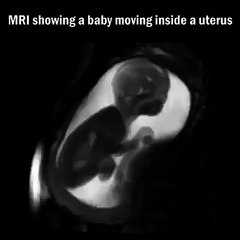

Le médecin saisit le bébé dans le ventre de la maman, ne le quittez surtout pas des yeux!

Pendant que sa femme visitait le médecin, Liam Muckleston a filmé la procédure du médecin de l’hôpital Sussex Royal de Brighton au Royaume-Uni. br br La grossesse étant à 36 semaines, le bébé se présente par le siège. Dans de telles circonstances, on préfère procéder à un accouchement par césarienne, afin d’éviter des complications comme le prolapsus du cordon ombilical, le manque d’oxygène et des blessures au crâne. br br Mais il est possible de retourner le bébé dans la bonne position et c’est ce que ce médecin va faire. br br La manipulation, appelée version céphalique externe (ou ECV), se fait en quelques minutes et est impressionnante. On commence par une injection, qui permet de détendre l’utérus et prévenir les contractions. Puis, à main nue, le médecin pousse vers le bas, tout en faisant rouler le fœtus.